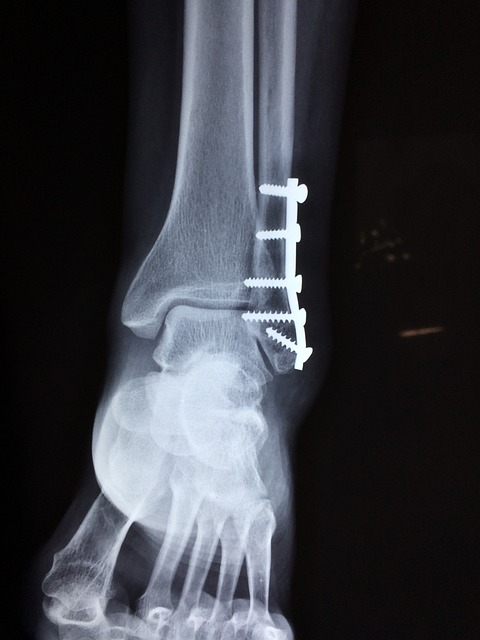

한방치료는 발목골절의 치료와 회복을 돕기 위해 다양한 효과적인 방법을 제공합니다. 한방치료는 주로 자연치료법과 약초, 마사지, 침술 등을 활용하여 통증 완화, 염증 감소, 혈액순환 촉진, 조직 재생 등을 돕는 원리로 작용합니다. 이를 통해 조기 회복과 합병증 예방에 도움을 줄 수 있습니다. 위의 사진과 같이 발목을 수술하는 것은 아무래도 리스크가 있을 가능성이 있기 때문에 한방치료를 적극 권장합니다.